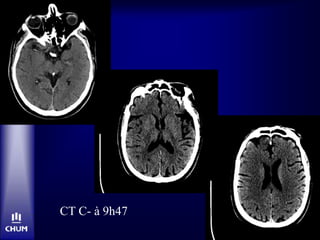

CT C- à 9h47

Bolus tPA-IV à 10h15